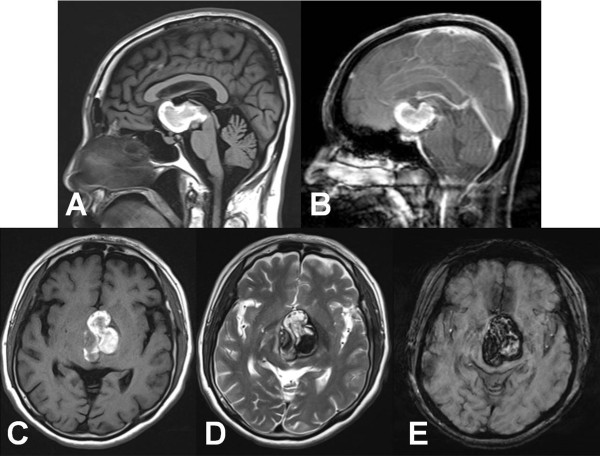

圖2:術(shù)前MRI圖像。矢狀面t1加權(quán)(A)和造影后t1加權(quán)(B)圖像顯示前三腦室和下丘腦區(qū)域非增強(qiáng)的出血腫塊。軸向t1加權(quán)(C)、t2加權(quán)(D)和易感性加權(quán)(E)圖像顯示典型??谞罨?,信號強(qiáng)度不均勻,含鐵血黃素邊緣提示混合急性期或亞急性期出血。